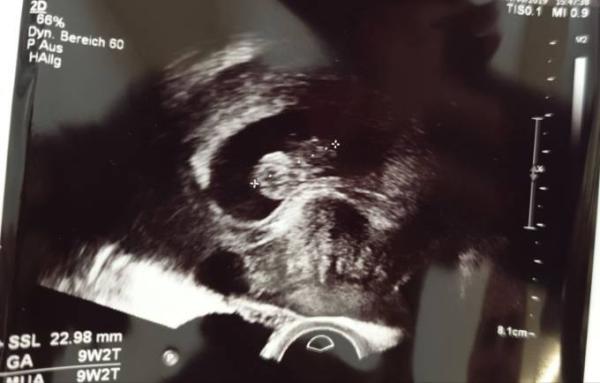

Hallo liebe JanuarMamis Wollte euch auch an meinem gestrigen Frauenarzttermin teilhaben lassen. War bei 9+3 bzw laut Computer 9+2 dort zum 2. Ultraschall und sie sagt, dass alles zeitgerecht entwickelt sei. Ich mache mir trotzdem Gedanken, völlig bekloppt, aber dachte es müsste schon größer sein das Murkelchen. Naja, wird schon alles passen. In 3 Wochen ist das 1.Trimesterscreening und dann mal schauen ob alles schicki ist. Schön positiv bleiben wa

Das sieht doch ganz hervorragend aus!? Was sagte die Ärztin denn, wie groß das Würmchen sein müsste? Ich freue mich jedenfalls für dich. Ungefähr um Die Zeit steht auch mein zweiter US an und wenn ich dein Bildchen so sehe, freue ich mich noch mehr darauf

Oh wie schön Ich denke die Größe passt, schon über 2 cm. Ab diesem Stadium sind die durchschnittlichen Größen nur noch Normangaben, weul sich jeder Embryo imdividuell entwickelt. Aber ich kann dich verstehen, ich mache mir auch ständig Sorgen. Nicht mehr lang, dann sind wir 12+